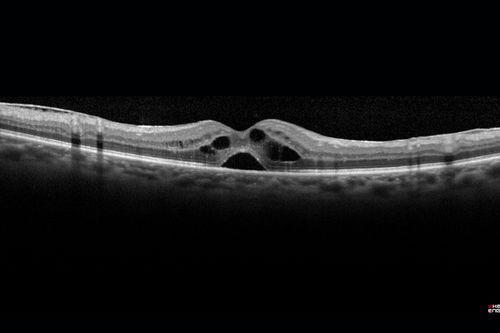

Pseudophakic Cystoid Macular Edema Both Eyes

81 year old man with vision loss about 4 months following ECCE. Did not respond to topical therapy but did fine with PST kenalog

Cystoid Macular Edema - Following Cataract Surgery - Both Eyes